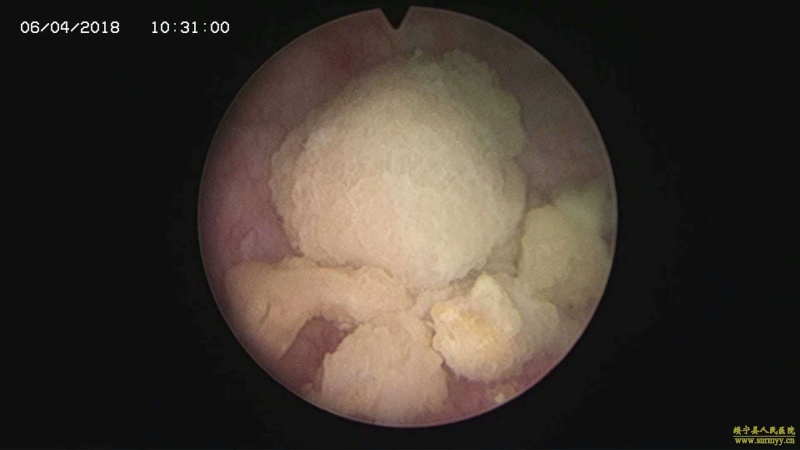

多镜联合治结石 4月6日,处于休假期间,但绥宁县人民医院泌尿外科的医护没有休息,在科主任张华生的带领下,打破常规,挑战高度,成功完成了一台复杂的结石手术。 据悉,患者姓杨,是一位60岁的男性患者,因"间断性左侧腰痛2年,再发伴尿痛2天"入院,经检查后发现患者左肾、左侧输尿管、膀胱内均有多发结石。针对这种结石,传统的手术方法至少需要开3刀,且需分期进行,使得患者痛苦大、治疗周期延长,费用也相应增高。肾结石开刀手术后劳动力会严重散失,即使采用现在流行的微创手术,常规也得分期进行,患者免不了多次手术的痛苦。为进一步减轻患者痛苦,绥宁县人民医院泌尿外科的医师们经过慎重考虑,决定打破常规,制定了多镜联合取石的手术方案。手术在4月6日顺利进行,术中联合膀胱镜、输尿管镜、经皮肾镜进行了长达70分钟的治疗,使得出血量不超过5mL且伤口仅0.5cm,一次性将患者膀胱,左侧输尿管,左肾结石全部取出。术后第五天经复查无任何结石残留,4月13日患者顺利出院。 目前,绥宁县人民医院泌尿外科在微创手术治疗各种尿路结石的技术上,己非常熟练。结石在整个邵阳地区发病率都很高,平常多喝水,每天饮水2000ml以上,调节饮食生活习惯,坚持锻炼可以有效预防结石发生,定期的健康体检也是预防结石的有效措施之一,可以早期发现结石,及时治疗。(图文 付志峰 编辑 谢雅玲) 图为:泌尿外科主任张华生、副主任付志峰进行手术时场景 图为:膀胱结石显象→手术碎石中显像→膀胱结石碎石后显像 图为:输尿管结石显像→输尿管结石碎石后显像 图为:肾结石显像→取出的肾结石标本 图为:术中建立穿刺通道 图为:术后留置的引流管 图为:术后伤口情况 |